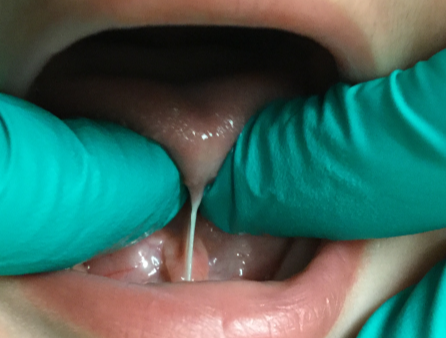

The full tongue tie was released on a newborn due to issues with nursing. Using a soft tissue laser, there is minimal bleeding after the procedure. Mom saw a significant improvement with nursing after the frenectomy was completed.